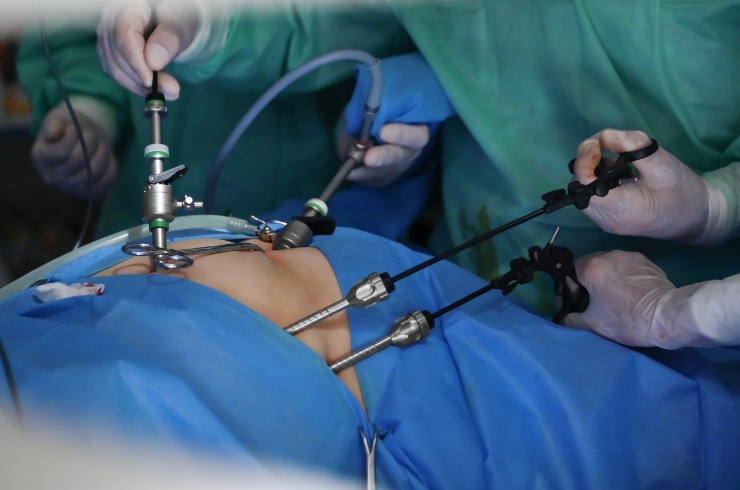

Minimally invasive and open surgical procedures ensuring faster recovery, reduced pain, and improved surgical outcomes with expert surgeons.